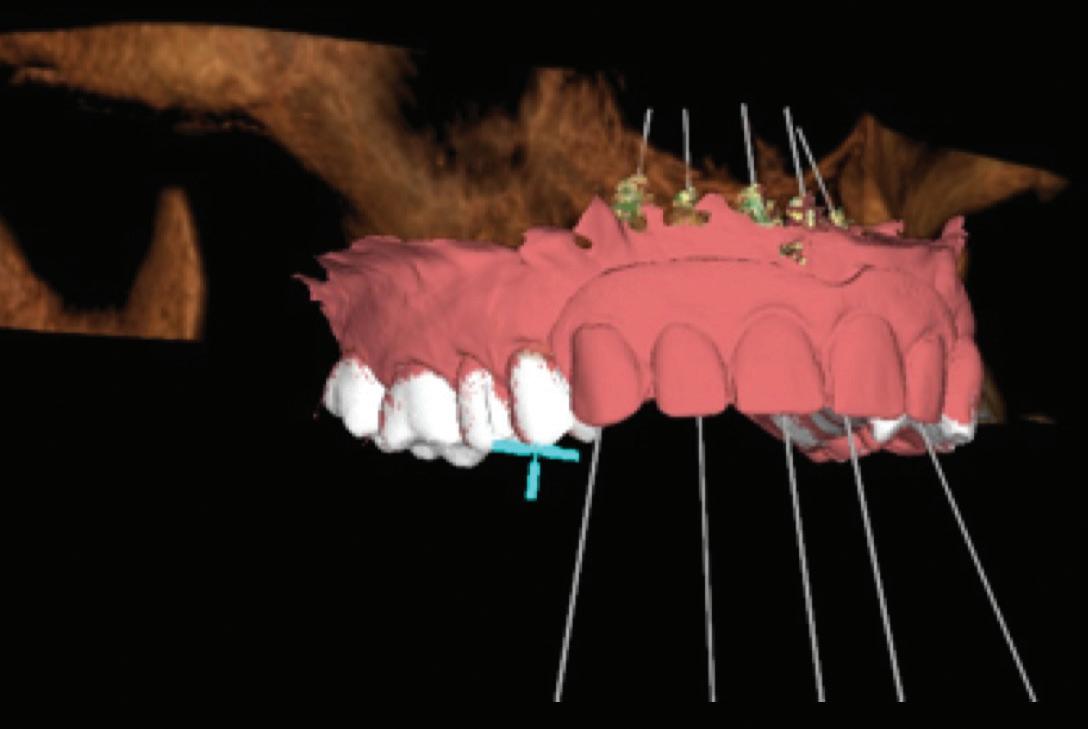

PROSTHETICALLY DRIVEN PLANNING

Tehnologia digitală redefinește terapiile implantare

• Chirurgia implantară cu cea mai inteligentă planificare și mai precisă execuție va necesita în continuare un finisaj protetic care funcționează biomecanic și realizează o estetică naturală ideală individuală. Dacă există un aspect al tratamentului protetic cu provocări în era digitală, acesta ar consta în munca artistică minuțioasă a ceramistului, cu modelarea și pictarea dinților pentru a imita natura.

Colaborarea profesională și planificarea ghidată protetic sunt esențiale pentru rezultate predictibile de succes.